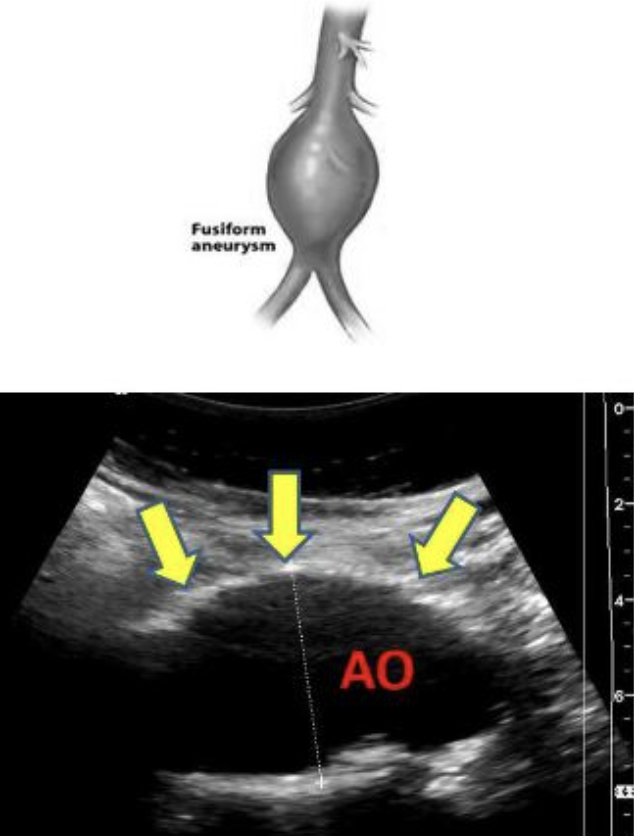

abdominal aortic aneurysm (AAA)

permanent localized dilation of AO when diameter is greater than 1.5x the proximal AO or is more than 3 cm

primary risk factors: dissection (3 types) and rupture

tx: surgical repair via graft placement

types of AAA

fusiform

fusiform aneurysm

circumferential enlargement of vessel with tapering at both ends

resembles a football